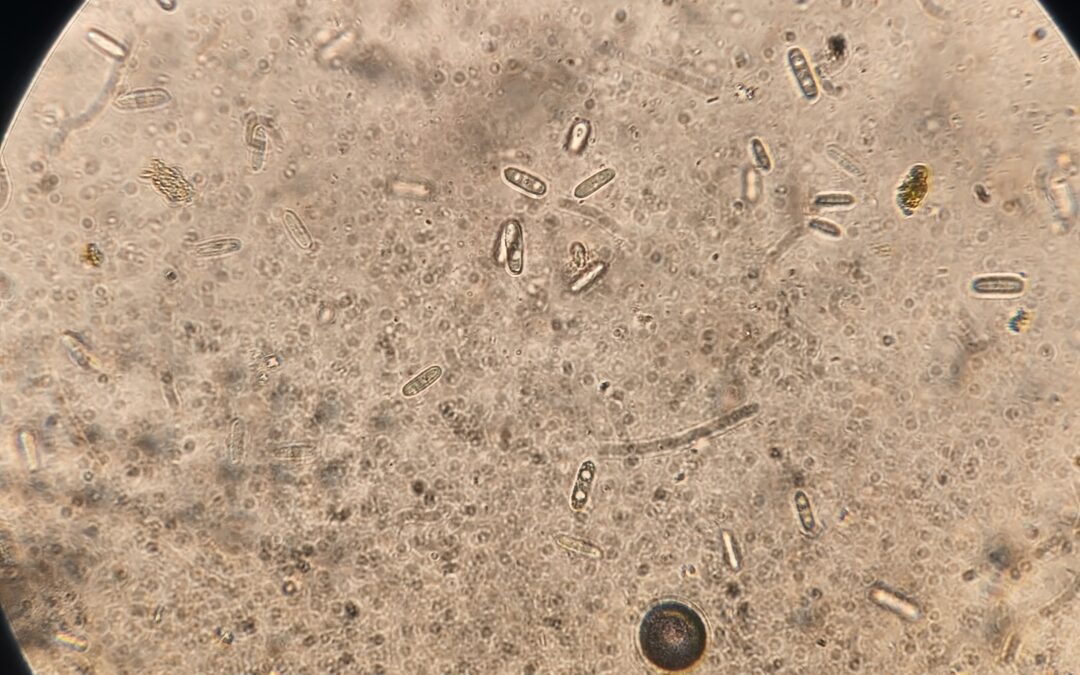

De nombreux examens complémentaires sont réalisés sur place : nombreux tests sanguins examens urinaires examens coprologiques (selles) en microscopie analyse d’eau pour les aquariums numération formule sanguine examen bio-chimiques sanguins dosage hormonaux...